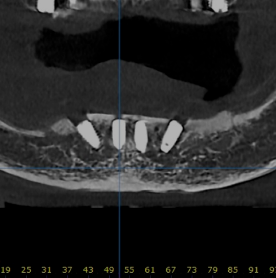

디지털 풀아치

할까? 말까?

틀니가 잘 빠지고 불편해서 고민이세요?

예전으로 돌아가고 싶으신가요?

갈비도 뜯고.. 입가에 주름도 없고 팽팽하던 그때로...

혹시 당신 혹은 부모님의 이야기인가요?

많은 분들의 걱정,

디지털 풀아치가 해결해 드립니다